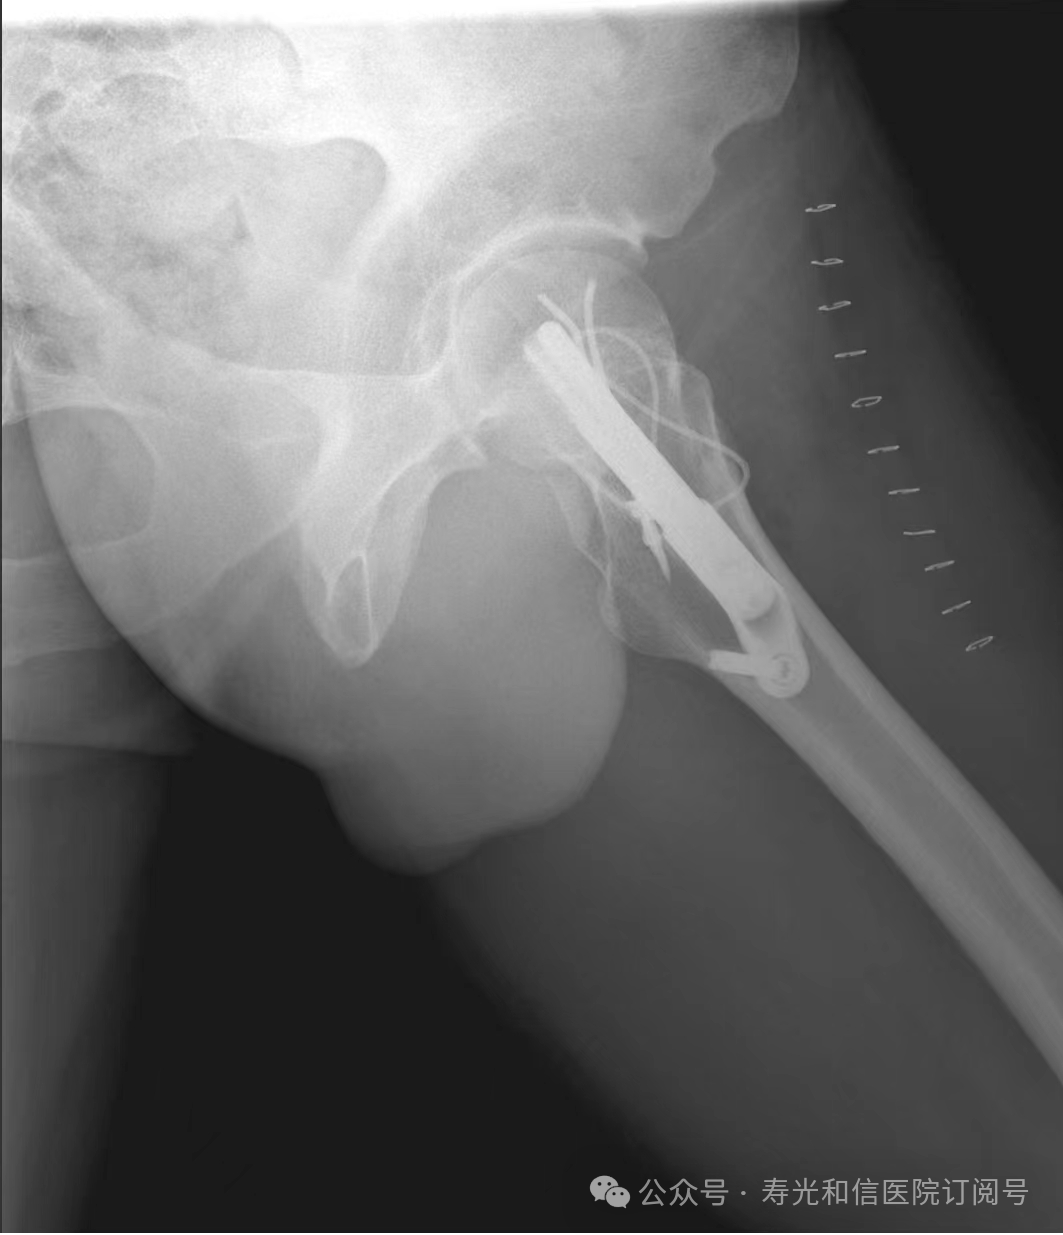

患者经120接诊,完善相关辅助检查后收入寿光和信医院骨外科。检查发现,患者右锁骨骨折、左股骨颈骨折、左大转子撕脱骨折、右膝关节前交叉韧带止点撕脱骨折、右膝关节外侧副韧带损伤、颅骨骨折及全身多处皮肤挫伤。因患者是外地来寿人员,家属短时间内不能赶过来,并且患者家庭经济条件较差,没有缴纳住院手术费的能力。但是股骨颈骨折后,股骨头坏死发生几率较高,手术越早进行,越有利于减少发生股骨头坏死的几率。骨外科主任李刚始终牢记救死扶伤的神圣职责,本着为病人负责的原则,坚定地选择先行为患者实行手术治疗。

与患者本人充分沟通后,李刚主任率领骨外科团队,经过充分的术前讨论及术前准备,于2024年9月1日为患者在全身麻醉下实施了4个半小时的内固定手术治疗。“时间就是生命”,手术过程中,全体参与人员密切观察病情变化,敏锐发现早期异常指标,争分夺秒,一丝不苟地做好各项抢救救治工作,做到瞬间判断、正确评估、果断处理,赢得了抢救患者的“黄金时机”,确保了手术的顺利完成。

在为其进行股骨颈骨折治疗时,手术团队为其采取了股骨颈动力交叉钉系统,这是一种新型股骨颈内固定系统,属微创植入,较从前的技术具有手术时间短、创伤小、力学稳定、滑动加压等优点。同时,患者恢复快,可早期离床、不负重下活动,缩短住院时间及康复时间,有效降低患者股骨颈骨折不愈合发生率,降低长期卧床合并症和死亡率。